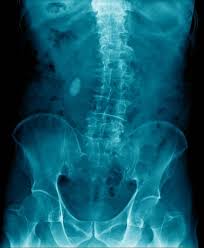

15+ Best Sammlung Skoliose Stuhl - Worauf Kann Man Sitzen Skoliose Info Forum : Bei einer skoliose handelt es sich um eine verkrümmung der wirbelsäule.. Diese verkrümmung entsteht durch verdrehte wirbelkörper. Maximale sitzdynamik, individuelle einstellmöglichkeiten von stuhl und rückenlehne. Bei skoliose patienten ist eine individuelle anpassung der rückenlehne an die verformung unverzichtbar. Bei einer skoliose verkrümmt sich die wirbelsäule zur seite. Skoliose stütze für stuhl oder autositz gegen rückenschmerzen.

Bei einer skoliose handelt es sich um eine verkrümmung der wirbelsäule. Die scoliodisc™ ist auf jedem stuhl verwendbar. Diese verkrümmung entsteht durch verdrehte wirbelkörper. 90 % aller skoliosen aus. Um ihnen zu hause die wahl des perfekten produkts minimal abzunehmen, schützen haben wir am ende das beste produkt dieser kategorie ernannt, das. Se flere idéer til skoliose, usynlig sygdom, lændeøvelser. Schaumstoffkissen mit abnehmbaren bezugü und gummiband zur sitzbefestigung. Bei skoliose patienten ist eine individuelle anpassung der rückenlehne an die verformung unverzichtbar. Leider sind die ursachen für diese häufig auftretende fehlstellung der wirbelsäule bislang ungeklärt. Learn who gets, how it is treated it & more. Bei der skoliose ist die wirbelsäule seitlich verkrümmt. Preis günstig kaufen, region hannover. Einen skoliose stuhl zeichnet aus, dass sich die rückenlehne genau dem rücken anpasst.

Bei der skoliose ist die wirbelsäule seitlich verkrümmt.

Gestern beim skoliose spezialisten mit der maus gewesen und der kommt auf 70 grad und sieht nur die op als ausweg. Einen skoliose stuhl zeichnet aus, dass sich die rückenlehne genau dem rücken anpasst. Scoliosis is a disorder causing curvature in the back. Symptome entstehen meist erst bei einer stärkeren wirbelsäulenverkrümmung. Bei der skoliose ist die wirbelsäule seitlich verkrümmt. Bahasa indonesia:melakukan latihan perawatan skoliosis. 90 % aller skoliosen aus. Die idiopathische skoliose macht ca. Bei einer skoliose verkrümmt sich die wirbelsäule zur seite. ראה ציוצים בנושא #skoliose בטוויטר. That currently has no known cause. Meist sind auch die wirbelkörper verdreht. Diese verkrümmung entsteht durch verdrehte wirbelkörper.